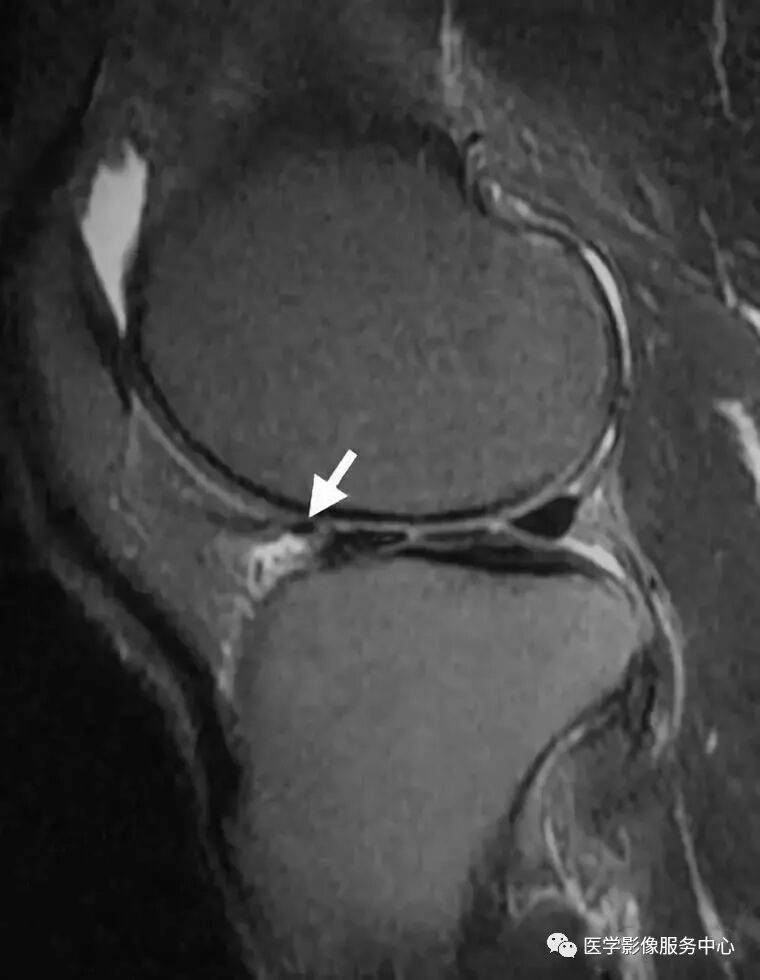

白色箭头所标记为膝横韧带

白色箭头所指为横韧带,黑色箭头所指为内侧半月板前角,位于横韧带正后方

白色箭头所指为横韧带,外侧半月板前角位于横韧带后方

膝横韧带经常容易被误诊为半月板前角撕裂或损伤,我们需要知道有这根韧带,而且要知道它特殊的解剖位置和半月板的形态是否正常,从而与半月板前角鉴别;